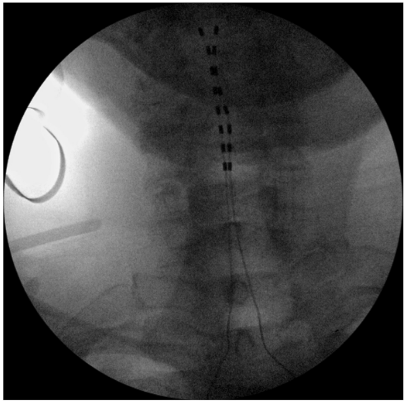

图片

电极植入位置